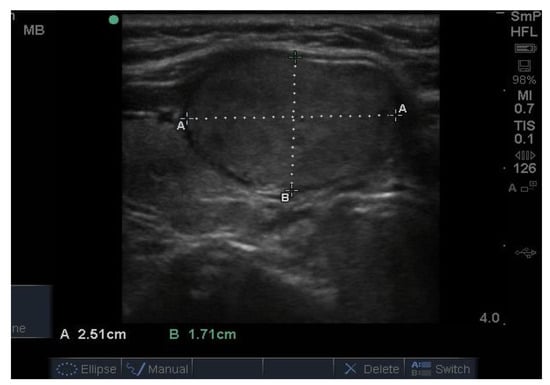

14. Parathyroid Disease

Because the senior author (JW) routinely measures serum calcium, parathyroid hormone (PTH) and vitamin D in his patients, hyperparathyroidism due to a benign adenoma of one of the parathyroid glands appears to be much more common than previously thought. The parathyroid glands are hidden behind the thyroid and so may be obscured by thyroid nodules, although they can often be seen in the longitudinal view below the lobes, as a hypoechoic lesion of around 1 cm in diameter (Figure 18).

Figure 18.

Thyroid ultrasound from a patient with hyperparathyroidism showing a hypoechoic lesion below the right thyroid lobe that was confirmed to be a parathyroid adenoma at surgery.

The parathyroid adenoma is typically hypoechoic by comparison to the nearby thyroid tissue, which is consistent with the author’s experience. However, only about 50% of subsequently proven parathyroid adenomas are seen on ultrasound and even the Sestamibi nuclear scan fails to pick them up in about 30% of cases.